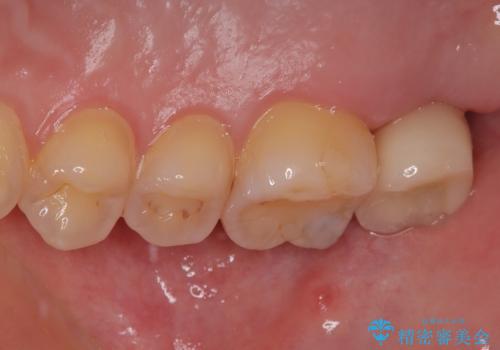

- 過去の歯医者通いの恐怖から虫歯を放置してきたものの、一大決心して来院された患者様です。

神経組織の失活している歯や歯根だけが残っている歯などがあり、全体的に歯石も多く付着している状態でした。